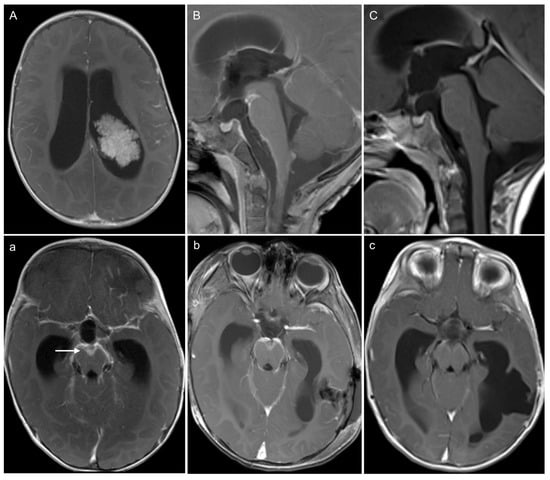

3.3. Leptomeningeal Dissemination (Table 2)

3.3.1. At Diagnosis

3.3.2. On Follow-Up